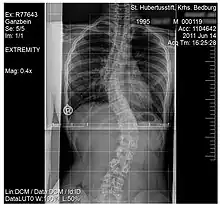

Scoliosis

Scoliosis, is a medical condition where a person's spine has several irregular curves that are located between the neck and the pelvis.[8] Symptoms of scoliosis in mild cases usually exhibit abnormal posture, back pain, tingling or numbness in the legs and in worse cases can exhibit breathing problems, fatigue, permanent deformities and in rare cases heart problems.[8]